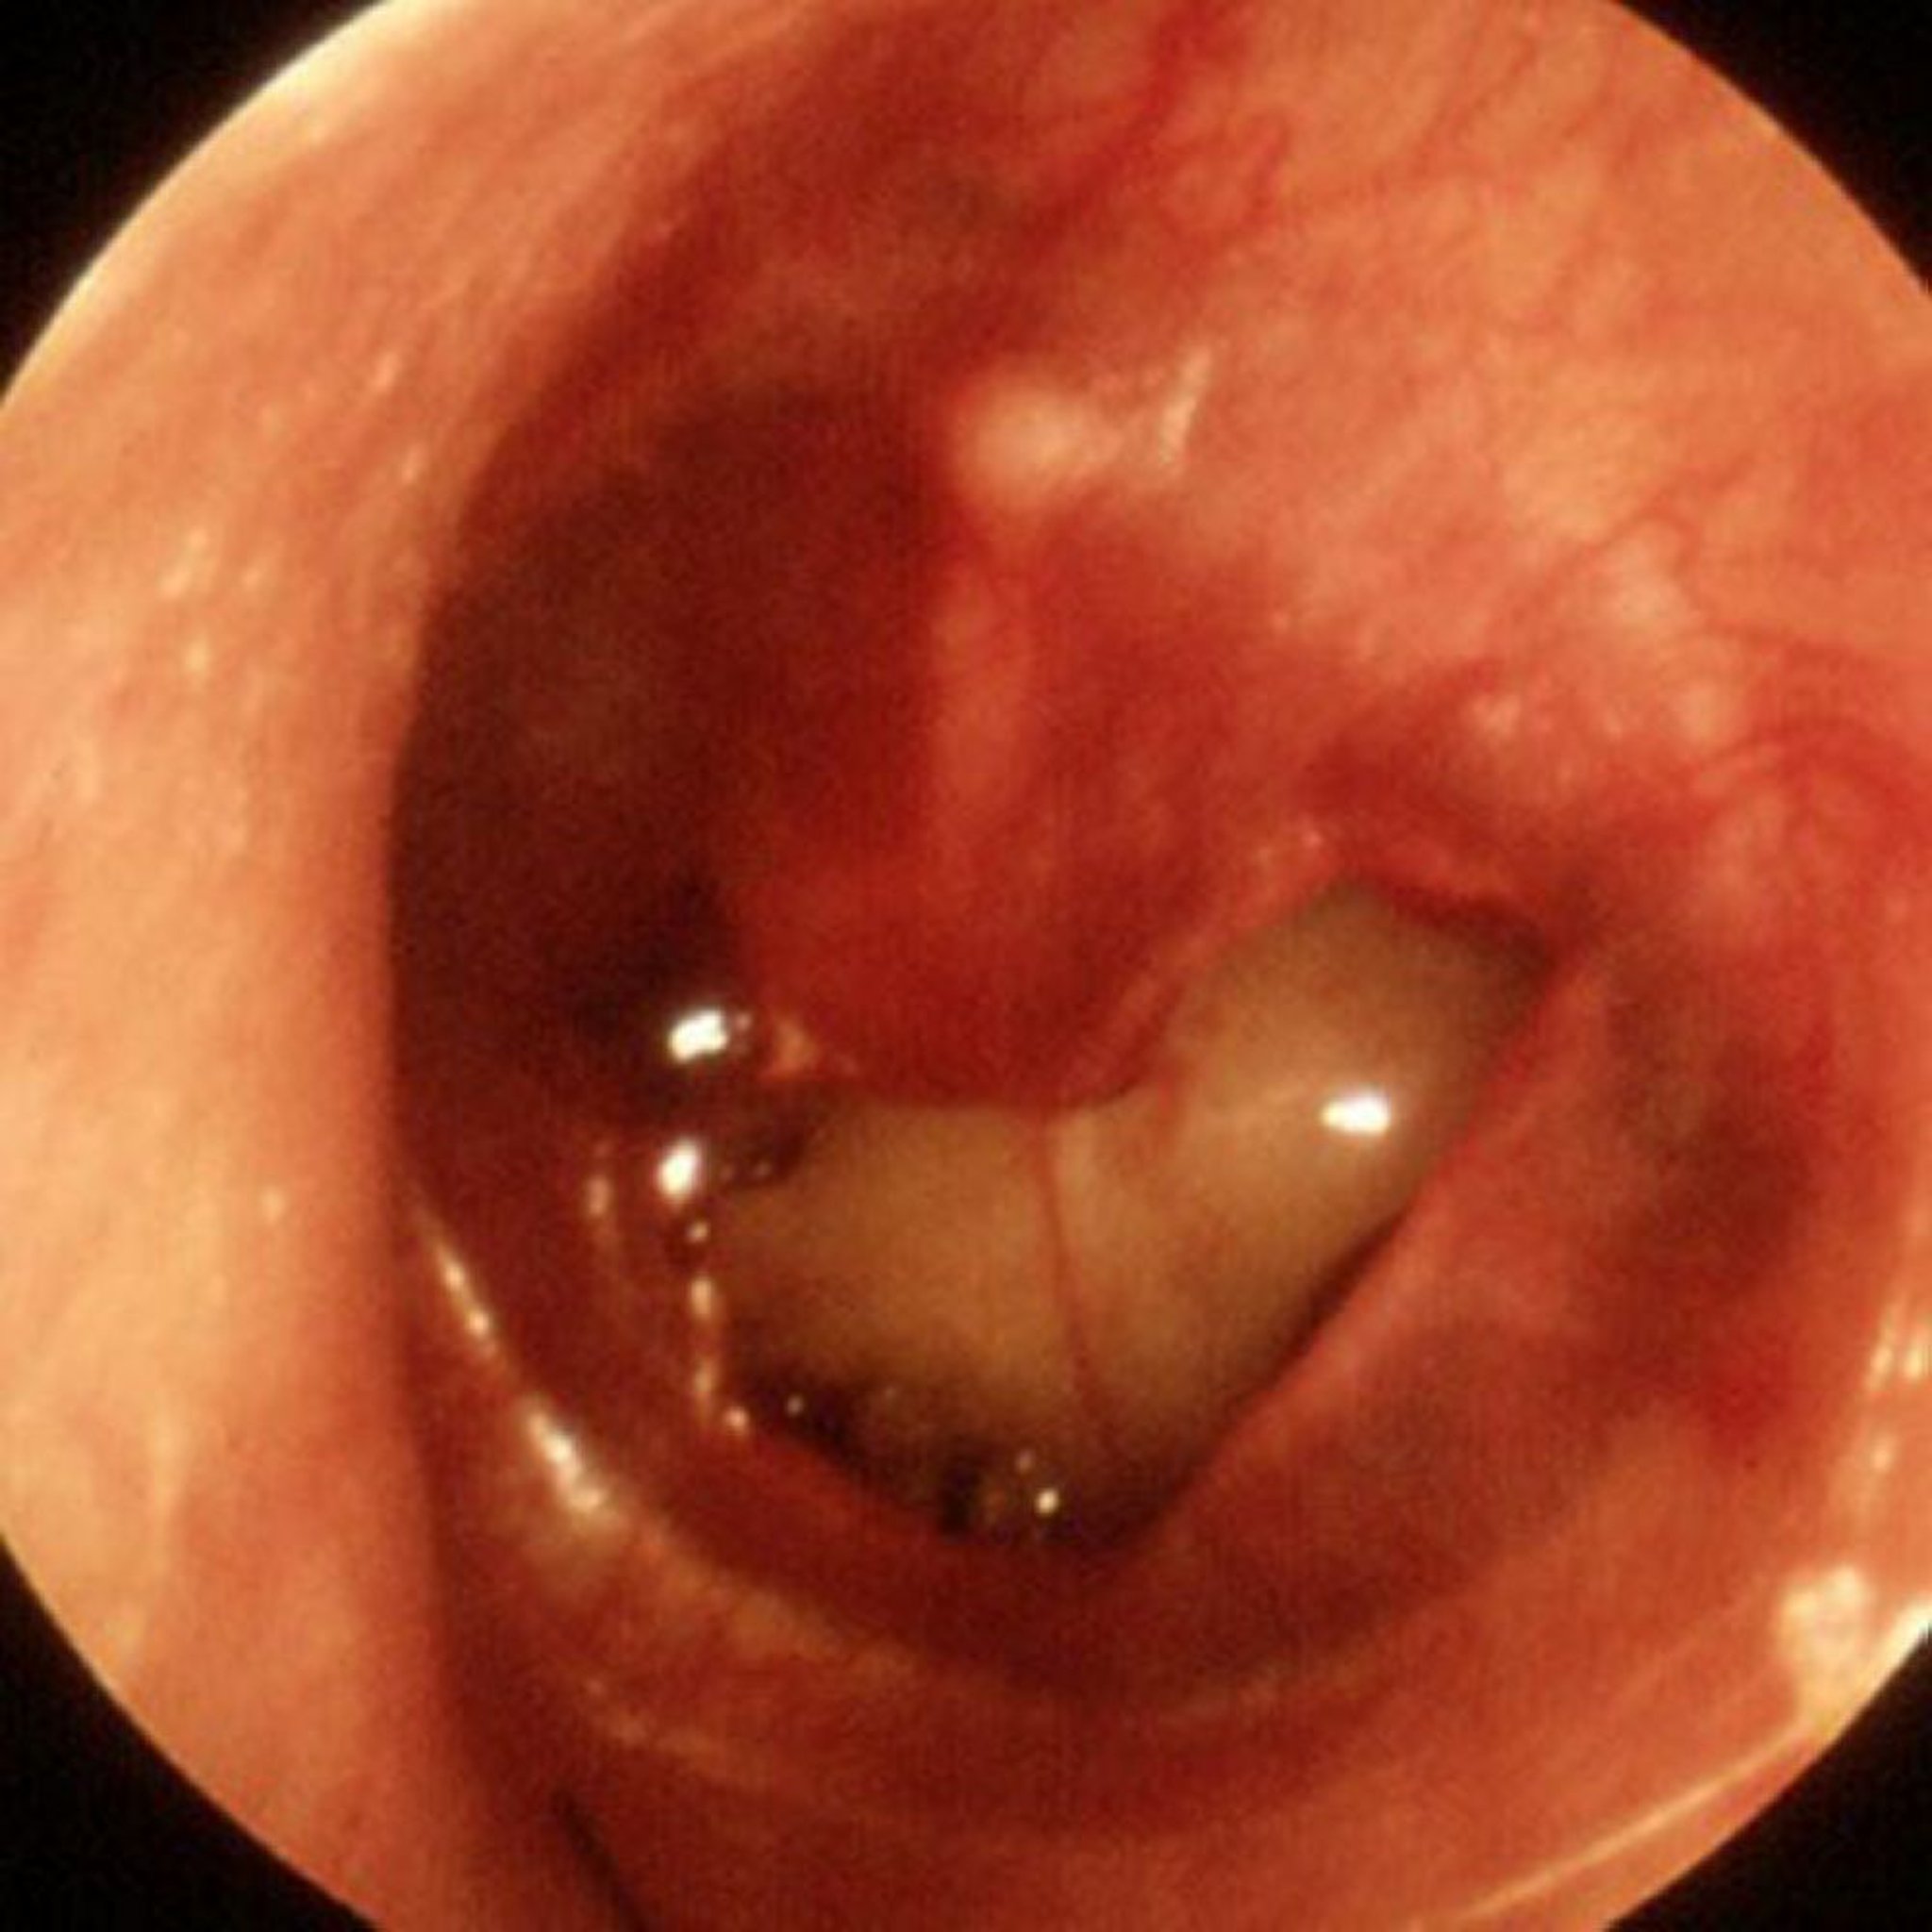

Traumatische Trommelfellperforation

In diesem Bild ist eine große traumatische Perforation zu sehen.

Abbildung zur Verfügung gestellt von Piet van Hasselt, MD.